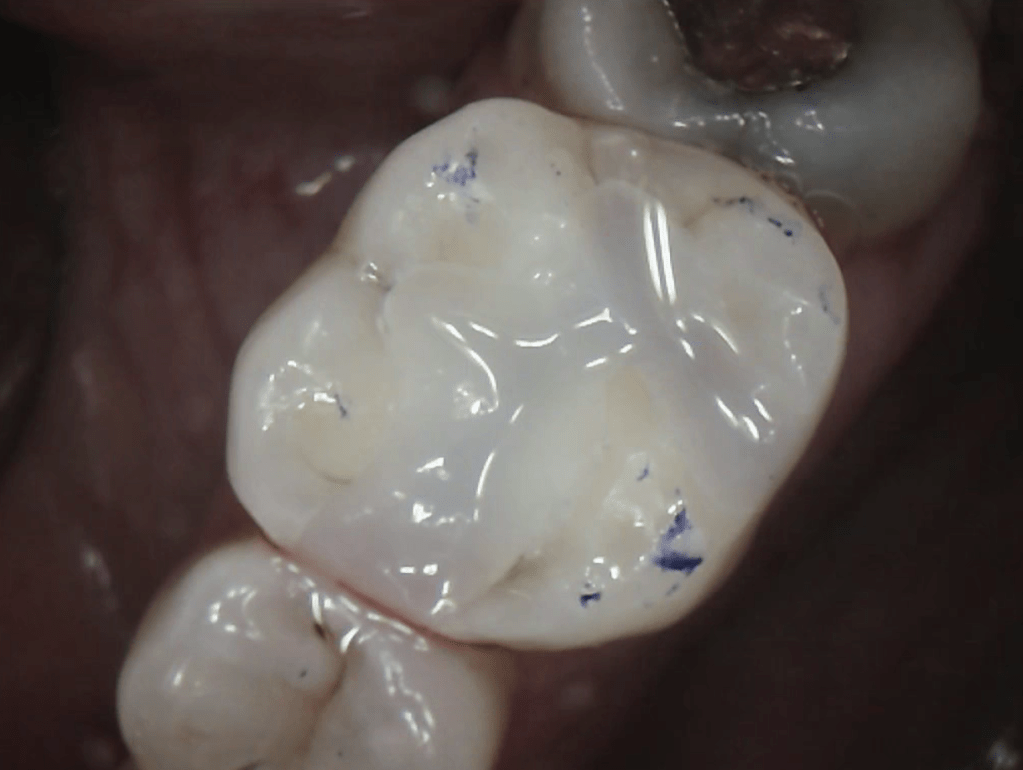

Cavity Broken Metal Filling

Fractured Tooth and Broken Metal Filling